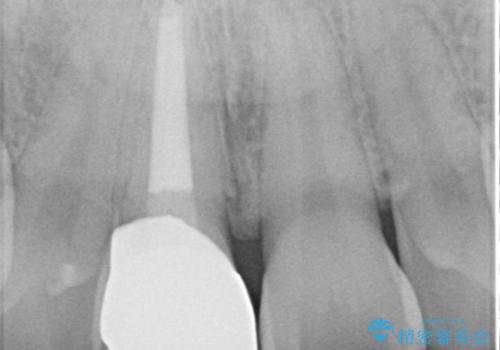

根管の中が空洞のままで被せ物と歯のきわも合っておらず適合が悪い状態でした。根尖部付近にはパーフォレーションリペア修復の痕がありました。バイオシーシーラーを使用しシングルポイント法で充填しました。空洞があると細菌が増える環境になってしまうので、根管治療からやり直し、緊密に充填しました。被せ物の見た目も大変満足していただけました。